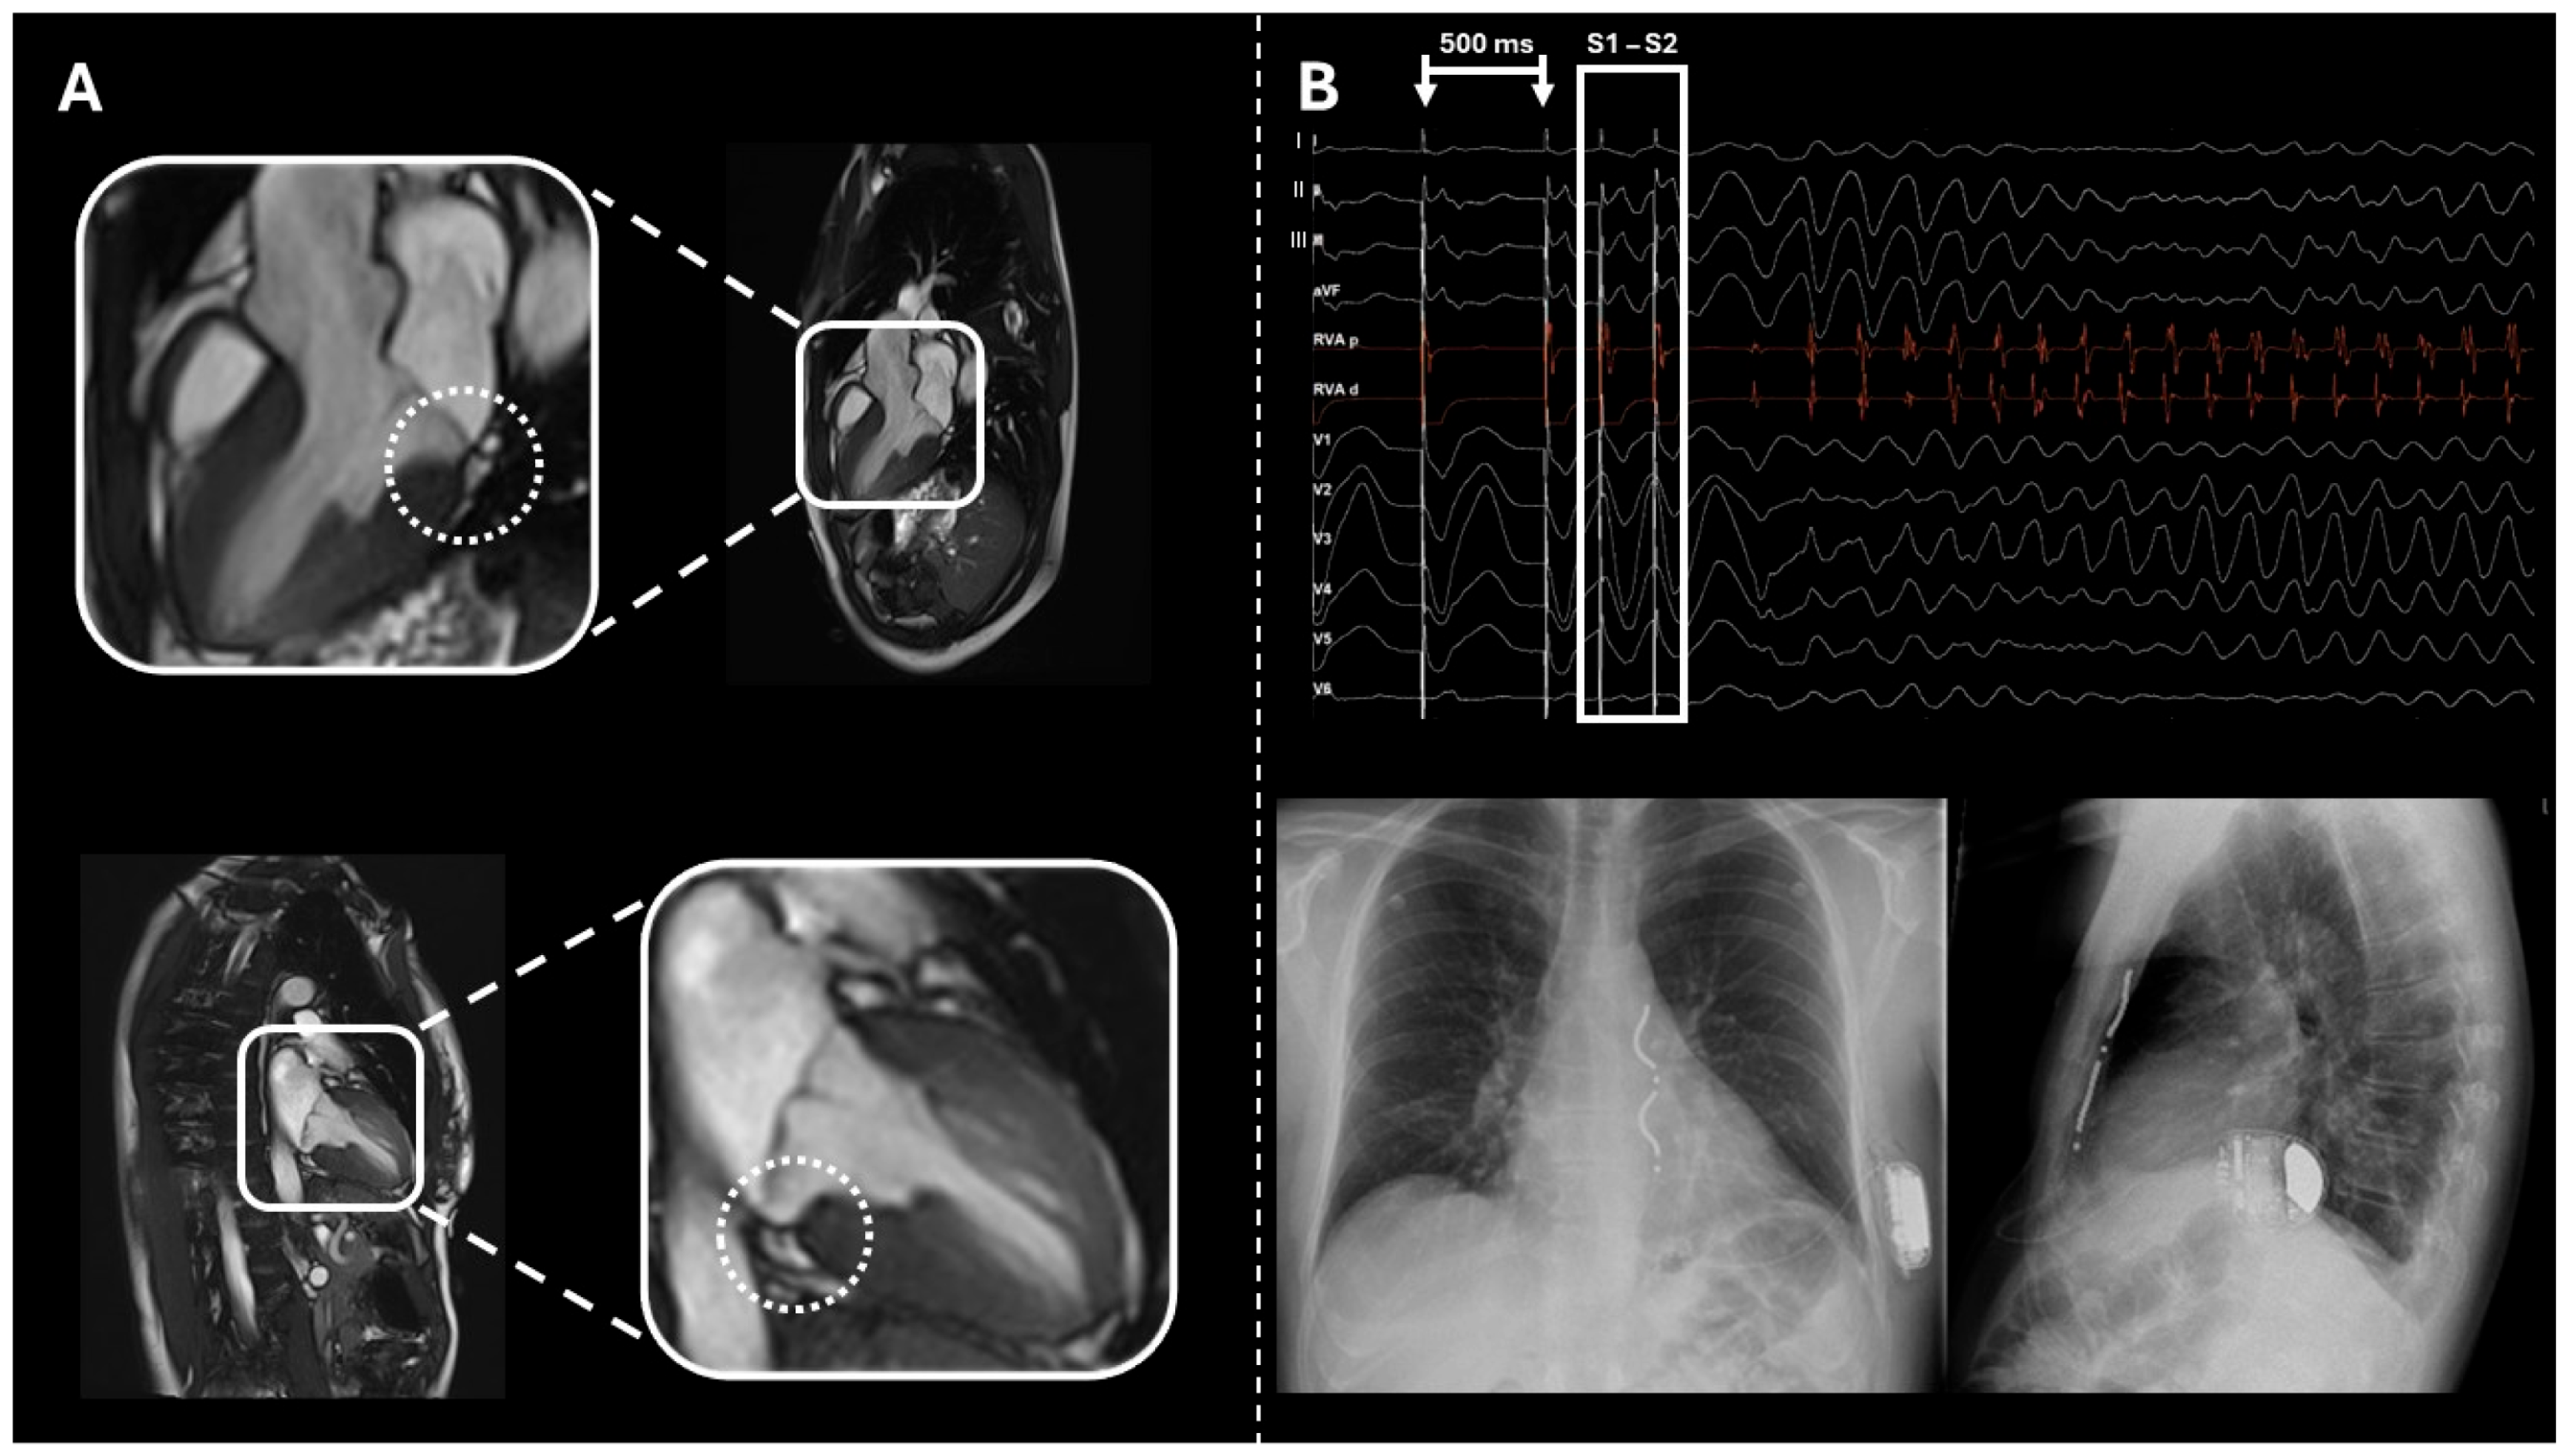

2.3. Case 3